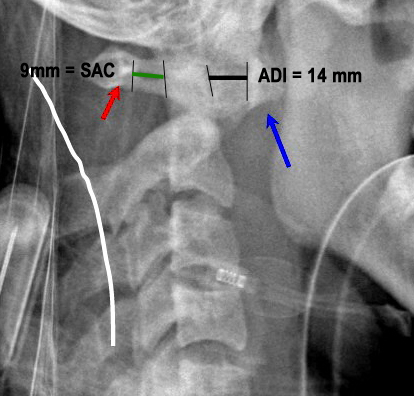

PADI>14mm

Boden and associates’ article presents compelling evidence that patients with rheumatoid arthritis and neurologic deterioration in C1-2 instability are more likely to achieve some improvement if the posterior atlanto-dens interval is greater than 10 mm on preoperative studies. All the patients in their series who had neurologic deterioration and a preoperative posterior atlanto-dens interval of greater than 14 mm achieved complete motor recovery.

Boden et al. “The most important predictor of the potential for neurological recovery after the operation was the preoperative posterior atlanto-odontoid interval (PADI). In patients who had paralysis due to atlanto-axial subluxation, no recovery occurred if the PADI was less than 10mm, whereas recovery of at least one neurological class always occurred when the PADI was at least 10mm. All patients who had paralysis and a PADI or diameter of the subaxial canal of 14mm had complete motor recovery after the operation.” They found no correlation with the anterior atlanto-odontoid interval (ADI) with the severity of paralysis or the potential for recovery.

Xrays to determine AADI and PADI:

- 3.5 mm on flex/ex

- PADI <14 mm more sensitive than AADI measurement for spinal cord compression in patients w/ RA. More sensitive for identifying patients at risk of neuro injury.

Xrays determine mechanical instability: c1-c2 relationship.

* AADI >9-10 mm= surgery due to risk of neurologic injury

* PADI <14 mm= surgery due to risk of neurologic injury

* 3.5 mm on flexion/ext views, though radiographic instability is common in RA and not necessarily indication for surgery.

PADI <14 mm more sensitive than AADI measurement for spinal cord compression in patients w/ RA. More sensitive for identifying patients at risk of neuro injury.